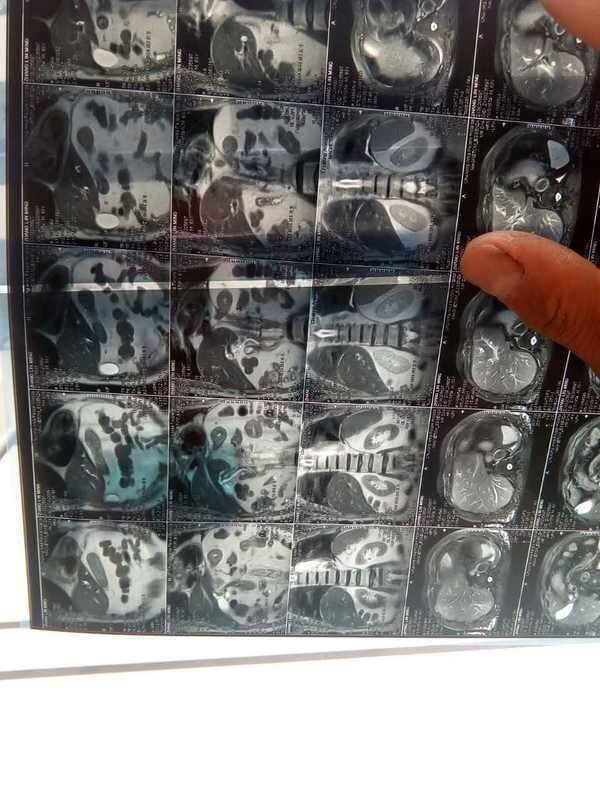

下面看看直接无法直视的!